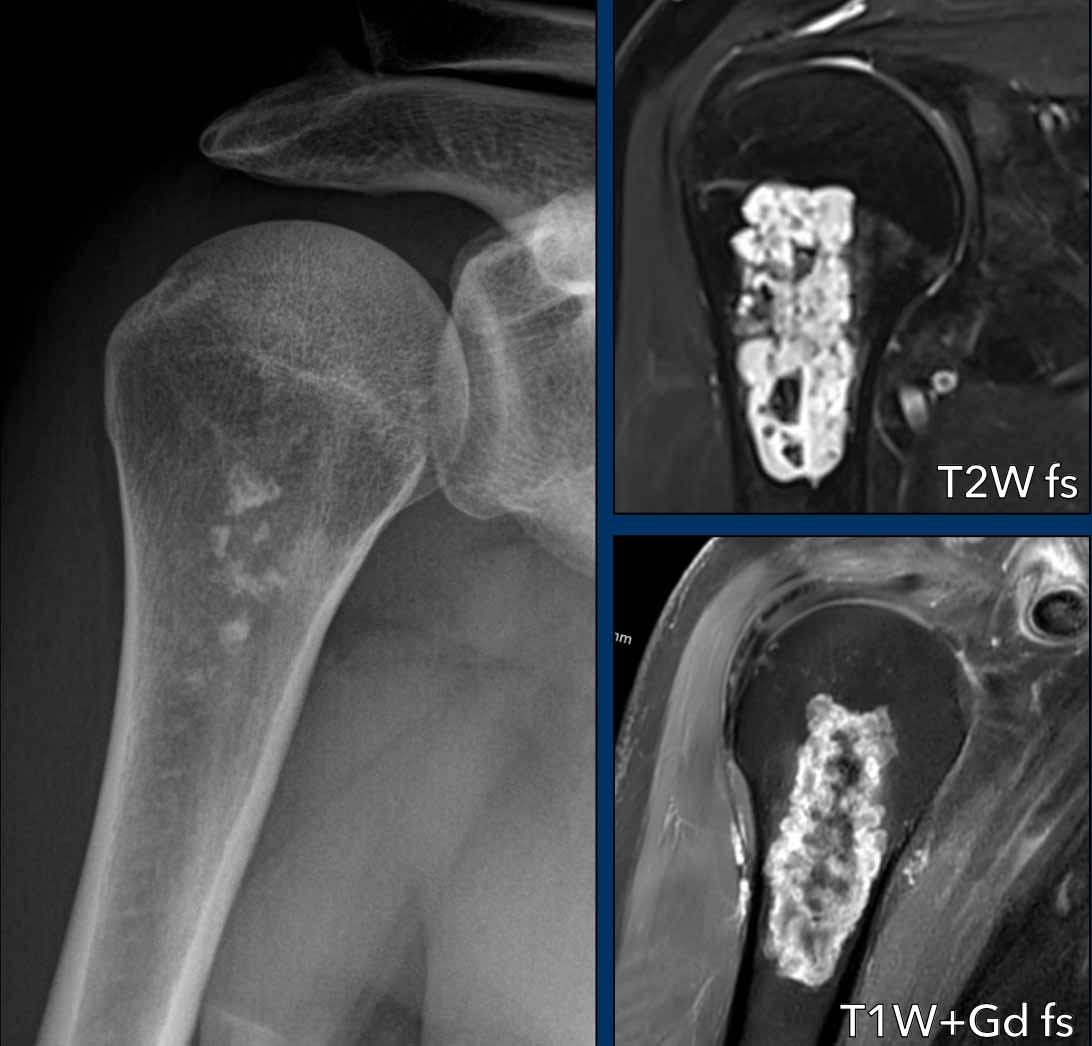

Phim X-quang cho thấy một tổn thương tiêu xương ở đầu xa xương đùi chứa các vôi hóa dạng bỏng ngô điển hình và có hình ảnh xói mòn vỏ xương phía trước (đầu mũi tên).

Trên MRI mặt phẳng đứng dọc, chúng ta có thể nhận thấy rằng khối u lớn hơn vùng vôi hóa trên phim X-quang, với kích thước 8 cm.

Khối u tăng tín hiệu trên T2 STIR và chứa nhiều ổ có tín hiệu thấp, tương ứng với các vôi hóa chất nền sụn trên phim X-quang.

Kết luận

Vì không có phản ứng màng xương hay khối phần mềm, các dấu hiệu này phù hợp với chẩn đoán ACT.

Bệnh nhân tiếp tục được theo dõi.